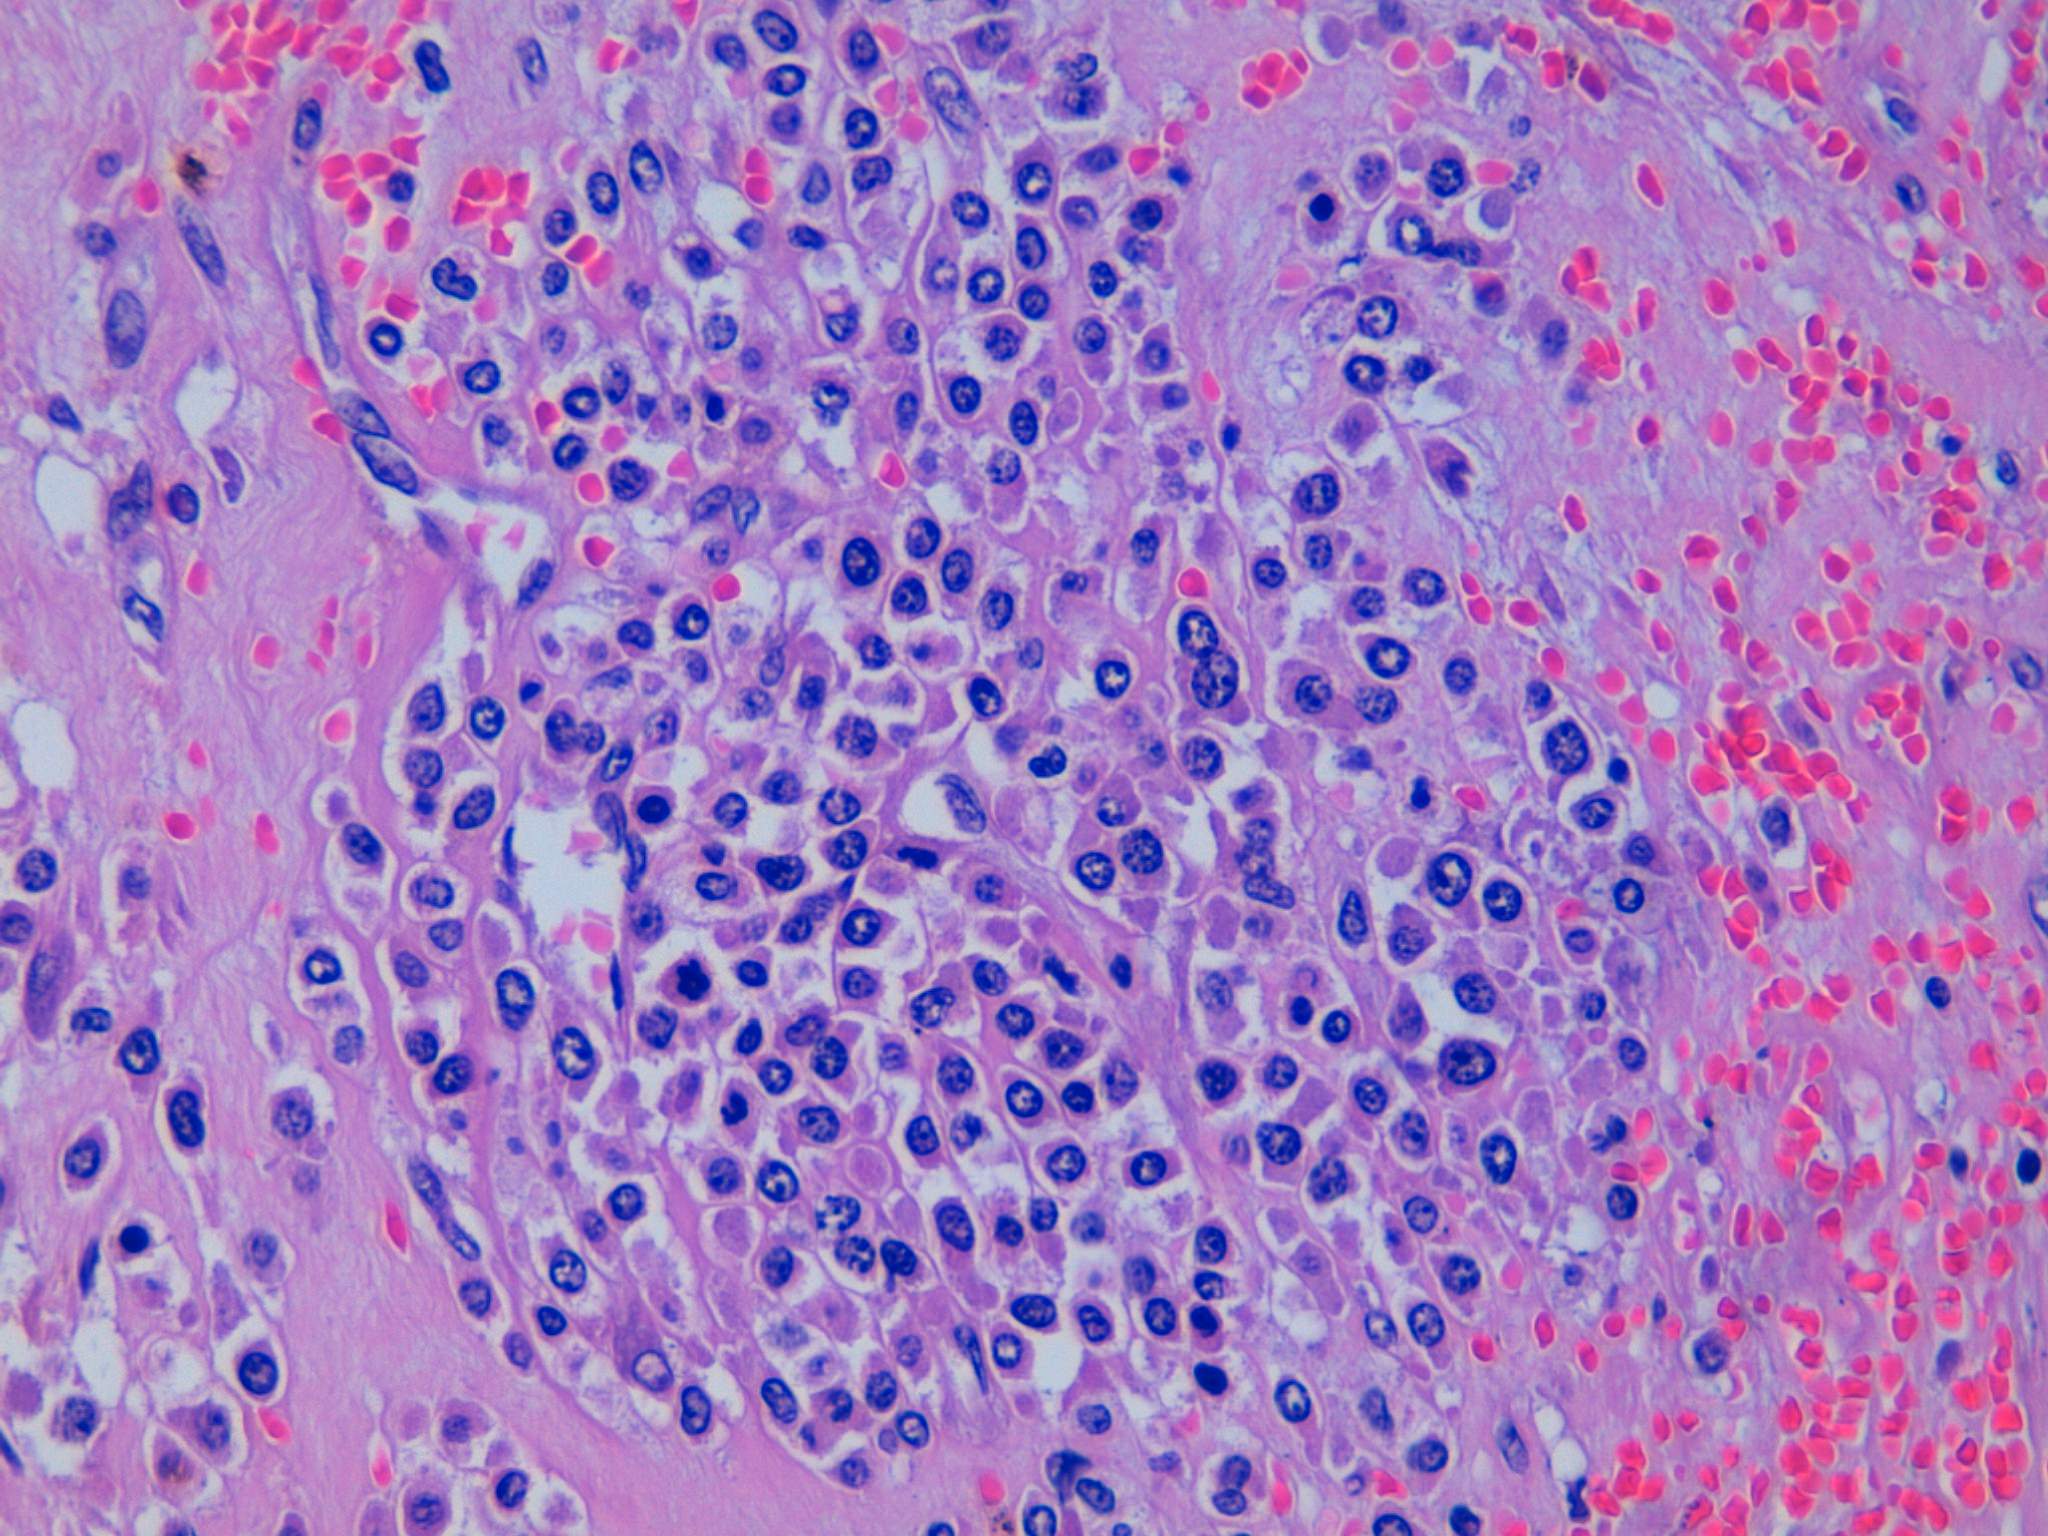

Webpathology.com: A Collection Of Surgical Pathology Images

www.webpathology.com

www.webpathology.com

uterus leiomyoma atypical bizarre webpathology pathology tumor comments

Webpathology.com: A Collection Of Surgical Pathology Images

www.webpathology.com

www.webpathology.com

uterus active webpathology leiomyoma slides pathology leiomyomas comments